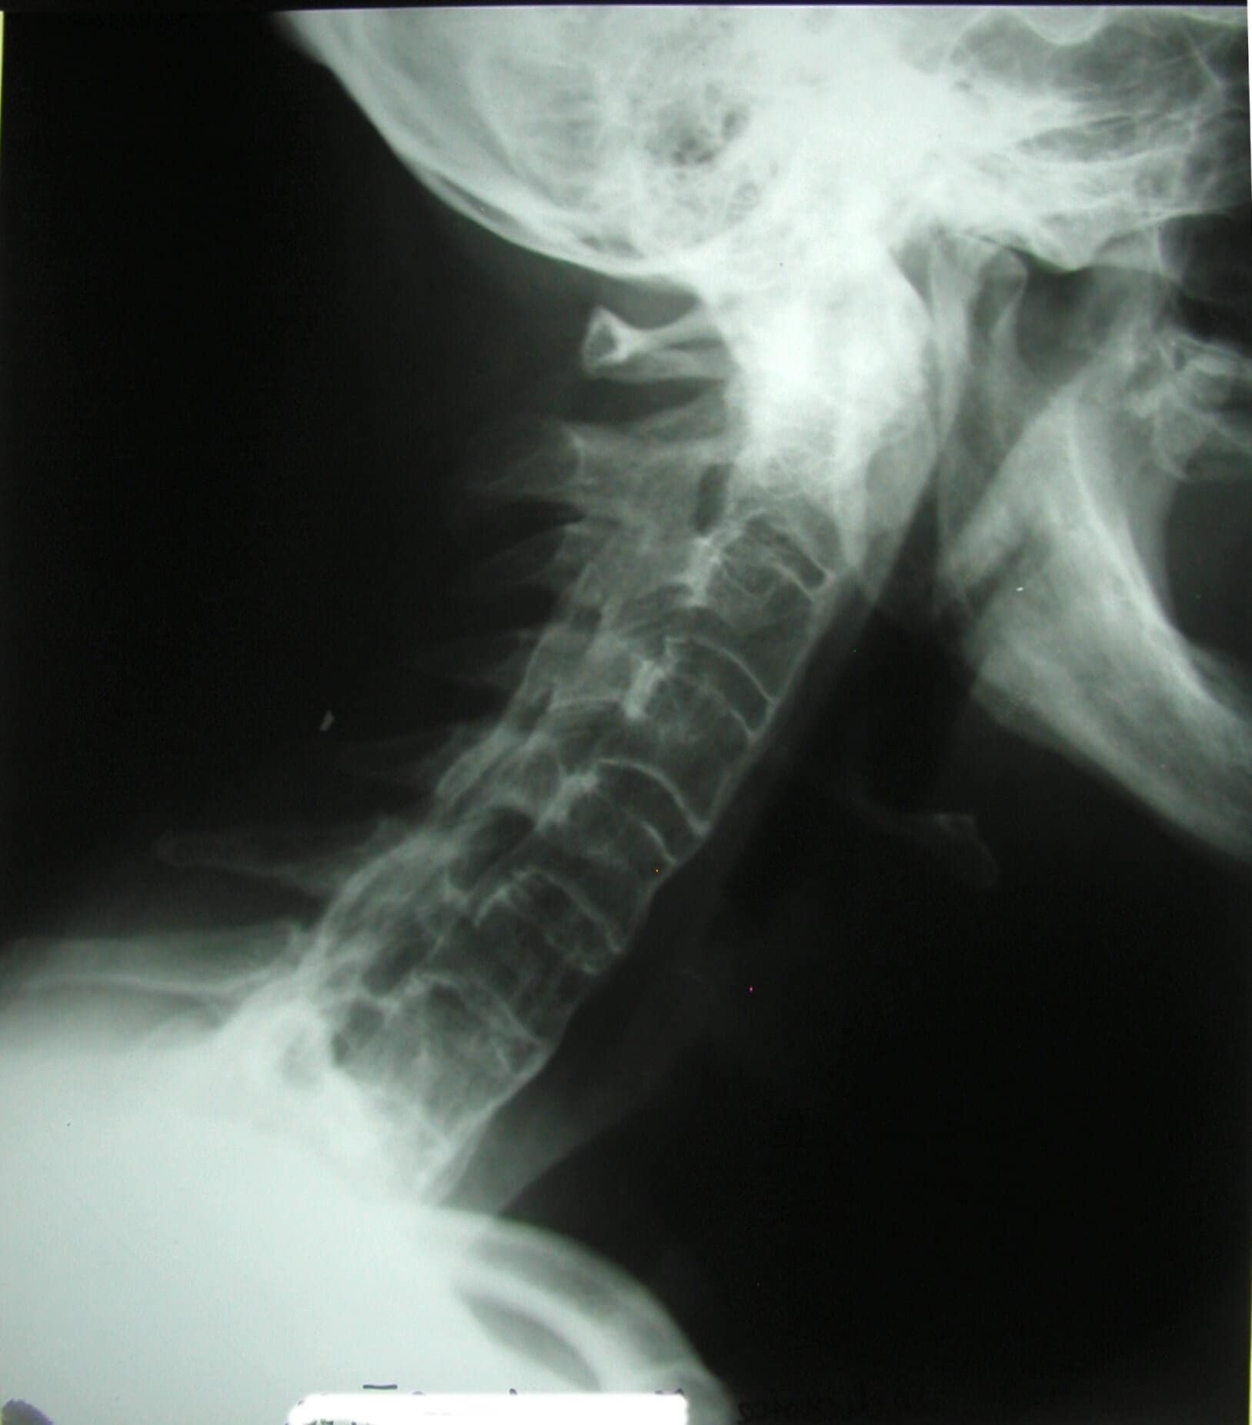

– Uram, ezek nem az ön felvételei… itt valami tévedés lesz…

– Ez egy gyerek gerince… a koponya és a csípőkép pedig…